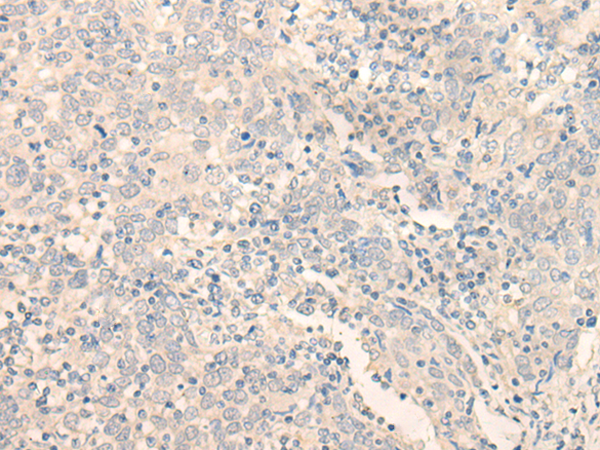

分类: 科研抗体货号: P09652别名: MIR1; GLFND应用: WB,IHC反应种属: Human, Mouse